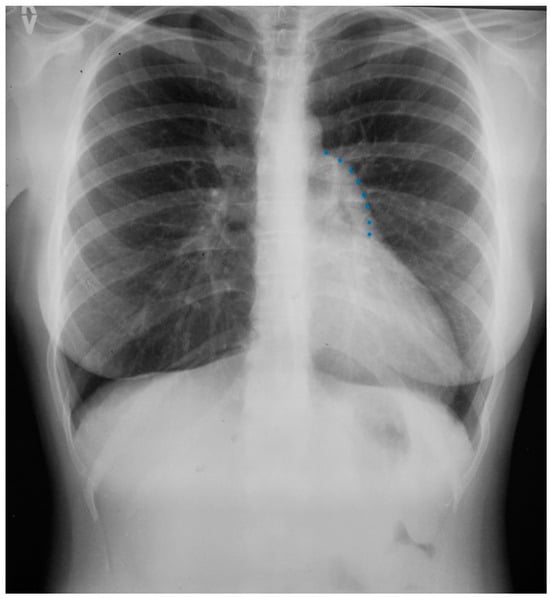

Sinus venosus atrial septal defect (SVASD) is the least common of the three main types of atrial septal defect (ostium secundum, ostium primum and sinus venosus). SVASD is located highest in the atrial septum and is also known as Defect Superior to Fossa Ovalis. This defect is in the region where the superior vena cava (SVC) joins the right atrium (Figure 8) and is often accompanied by anomalous termination of the right upper pulmonary vein(s) in the SVC near its right atrial junction or in the right atrium near the SVC junction [9]. As is seen in all ASDs, the resulting left-to-right shunting in SVASD increases the right atrial size and right ventricular size. A large shunt will present with dyspnea, fatigue, exercise intolerance, palpitations and/or syncope [7]. Physical examination may include a left parasternal heave, a pulmonary systolic flow murmur and fixed splitting of the second heart sound. The CXR may show right ventricular enlargement, right atrial enlargement, a prominent pulmonary artery segment and increased pulmonary vascularity (Figure 9). In the presence of a large left-to-right shunt, the volume of blood that is pumped to the lungs may be two or more times the volume pumped systemically. This is reflected on the PA CXR by the size of the pulmonary artery segment exceeding that of the aorta.

Figure 9.

Posteroanterior chest X-ray of sinus venosus atrial septal defect. This chest X-ray is of a 24-year-old female with a sinus venosus atrial septal defect and anomalous right upper pulmonary venous drainage to the superior vena cava. The image is well centered and there is a good inspiration. The cardiothoracic ratio is increased, the pulmonary artery segment is increased and the pulmonary vascularity is plethoric. Also note that there is a right-sided aortic arch (blue dots). This allows the enlarged pulmonary trunk to be better visualized because the thoracic aorta does not obscure it. Because she had dyspnea, fatigue and exercise intolerance she underwent surgical repair of the ASD and redirection of the right upper pulmonary vein to the left atrium. Her postoperative CXR showed decrease in C-T ratio and pulmonary vascularity. Her symptoms resolved.